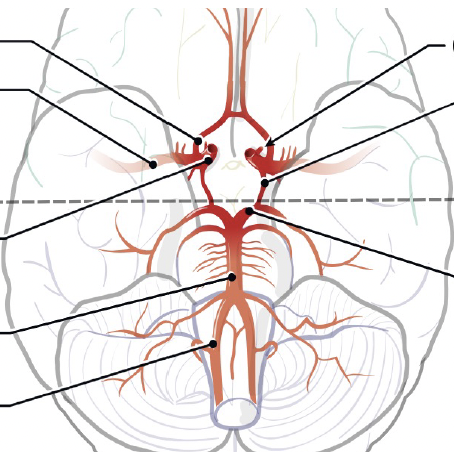

Q

ID the structures on ventral brainstem

A

How well did you know this?